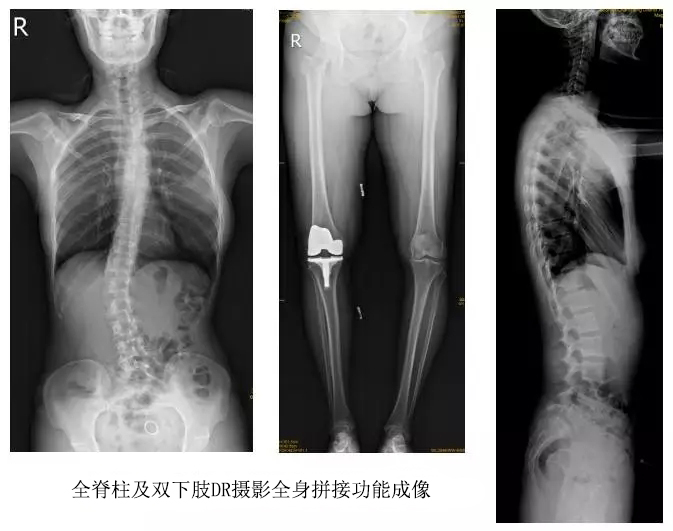

技術(shù)日新月異,隨著DR全身拼接功能的可實(shí)現(xiàn),有效解決了全脊柱及全下肢的完整成像。

以某院所攝X光片為例,對(duì)比傳統(tǒng)攝片與全身拼接功能的區(qū)別:

傳統(tǒng)X光片只能觀察每個(gè)部位的局部情況,無法在統(tǒng)一體上進(jìn)行連續(xù)、全面的觀察,全脊柱及下肢全長(zhǎng)片則能直觀的看到整體形變。通過DR全身拼接功能實(shí)現(xiàn)的完整成像,為診治脊柱及下肢畸形提供了完美的臨床影像依據(jù),對(duì)臨床診斷、術(shù)前手術(shù)方案的制定和術(shù)后療效的評(píng)估等臨床應(yīng)用具有十分重要的意義,有效滿足了此類疾病臨床診斷和治療的要求。

通過以上對(duì)比,可以發(fā)現(xiàn),在缺少DR全身拼接功能的條件下,傳統(tǒng)X光攝片無法有效解決骨科常見疾病如脊柱側(cè)彎及下肢畸形的臨床診斷。在國(guó)家大力推進(jìn)健康中國(guó)、人民不斷增長(zhǎng)的醫(yī)療需求的大背景下,醫(yī)療缺陷將不斷被合理技術(shù)替代,因此從對(duì)立面評(píng)測(cè),如今,沒有全身拼接功能的DR就不是合格的DR。